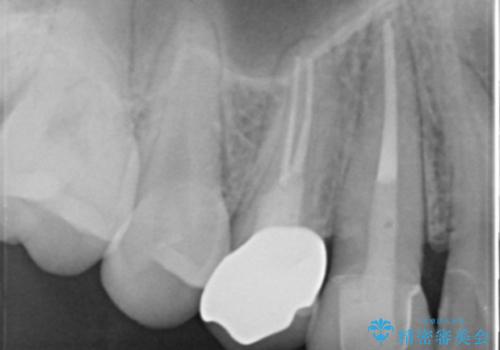

- 食事中に急に歯が折れ、周囲の歯も痛みだし治療を希望され来院されました。

ジルコニアクラウンによる咬合機能回復、根管治療を行い歯の痛みをとり長期的な予後の見込める治療を計画します。

- 26万円(仮歯・ファイバーコア・ジルコニアクラウン×2)費用は治療当時の料金となります